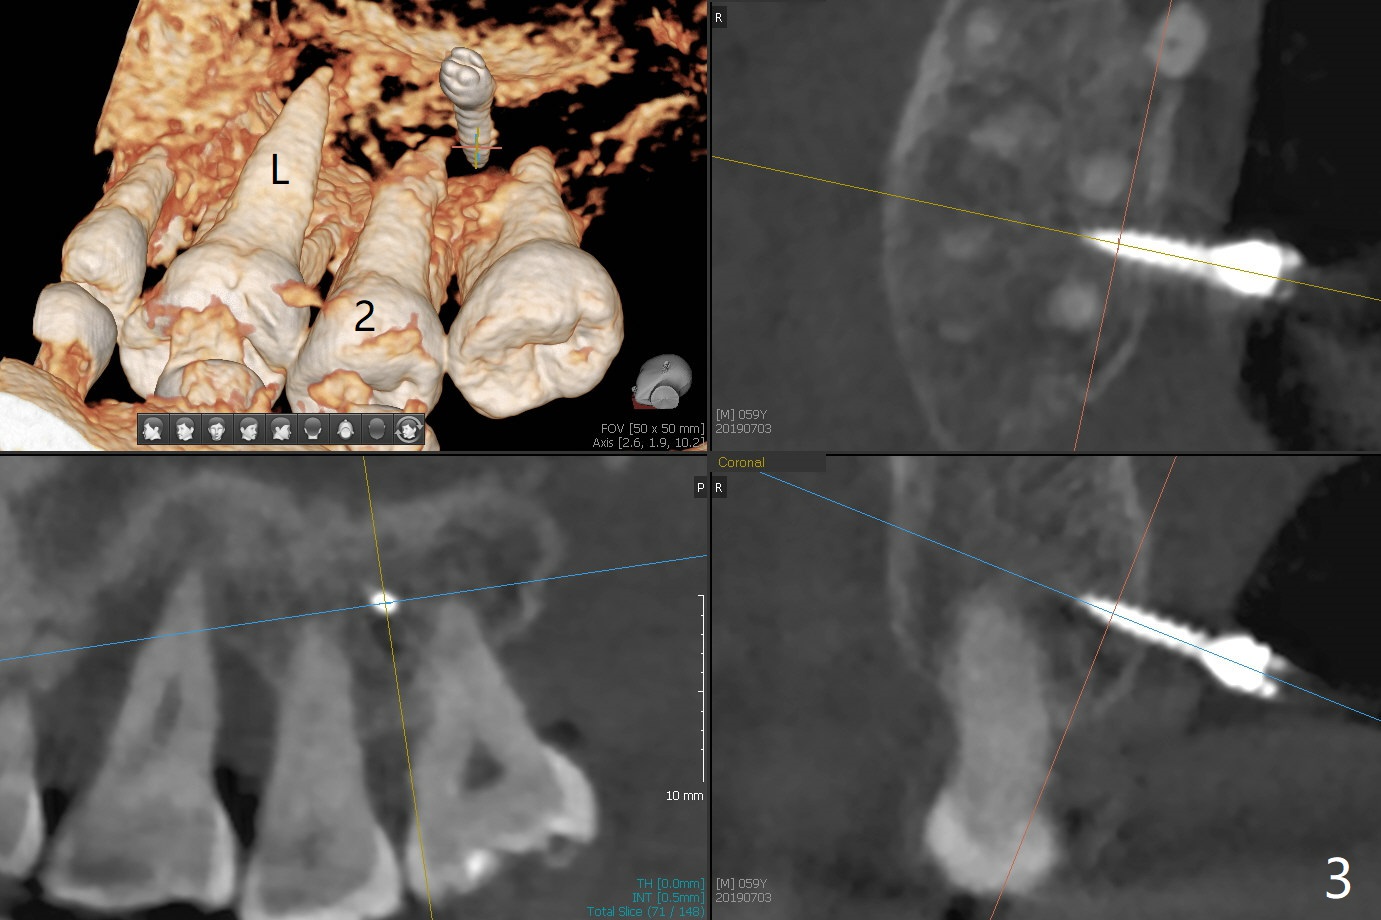

When 6 and 8 mm Tomas pins are initially placed mesiobuccal (MB) and distolingual (DL) to the supraerupted tooth #2, PA is taken (Fig.1), which shows that the DL one seems too distal. The mini implant is removed and placed more mesial (Fig.2, 7 (^: original entry)). When the patient experiences a little pain as the DL implant is being placed deeper with minimal local anesthetic, CT is taken. In fact the latter is between the apices of the teeth #1 and 2 (Fig.3 (L: lingual view of 3D image)). The implant is later placed deeper with minor angular change as well as more anesthetic. There is an advantage to place the miniimplants apically; there is more space. But the MB implant is a little bit mesial (Fig.4). After withdrawal, the trajectory of the implant is changed somewhat as indicated by a red arrow in Fig.5). Note the apical placement of the minimplants (close to mucogingival junction, Fig.6,7).